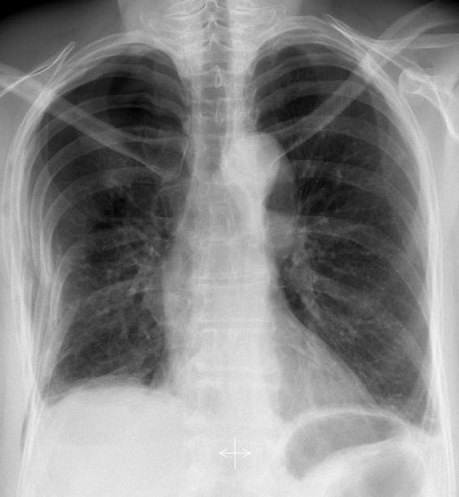

Image

radiologique cliche de face PA d'une pneumothorax du

poumon droit avec aspect de collabe legere du poumon

droit avec de zone peripherique pulmonaire n'a pas

de trame de parenchyme du pomon droit . Il est un

peut de difficile de interpreter et observer

la limite du plevre visceral pulmonaire |

Aspect radiologique de même

cas avec image de collabe du poumon droit , le

mediastin devie vers à gauche . On peut en s'observe

la limite hyperdense de la plevre visceral du poumon

droit tres nette et facilement . Image radiologique

TDM en coupe axial fenetre parenchymateuse |